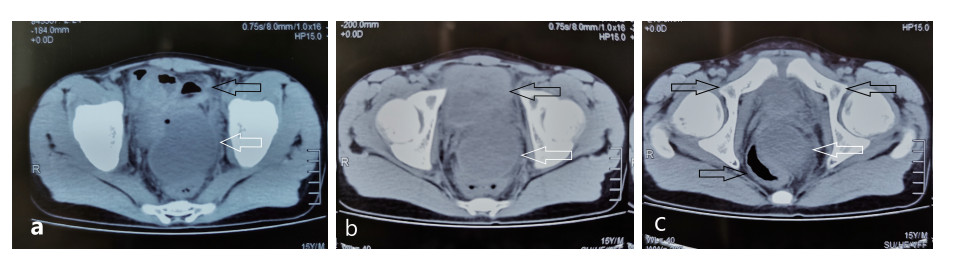

患者入院后完善相关检查,血常规:白细胞6.73×109/L,中性粒细胞4.87×109/L,血小板126×109/L;C-反应蛋白 > 90 mg/L;降钙素原7.6 ng/mL;凝血功能:PT 15 s。盆腔超声显示:骶前间隙可见一80 mm×46 mm的无回声区,内可见斑点样中强回声(图 2)。排除禁忌后,于入院当晚行超声引导下穿刺置管引流术,由于脓肿位置较深,经腹途径有肠管﹑膀胱和直肠的遮挡,所以本中心决定选择超声引导下经臀穿刺引流术。

| 图 2 盆腔超声显示:骶前间隙可见一80 mm×46 mm的无回声区,内可见斑点样中强回声 |